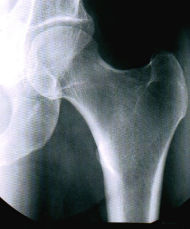

Denn der Radiologe macht normalerweise nur Aufnahmen von Knochen und Skelettteilen, die durch Haut und Fleisch nicht mit dem Auge zu sehen sind. Haut und Fleisch fehlen mir aber wie du sicherlich schon festgestellt hast.

Er hat dann aber doch zwei Aufnahmen von mir gemacht und mir erklärt, was man erkennen kann. Ich war allerdings so aufgeregt, dass ich es vergessen habe. Betrachte die Aufnahme. Kannst du mir helfen?

3. Speichere das Bild unter dem Namen des Knochens, der auf der Röntgenaufnahme zu sehen ist.